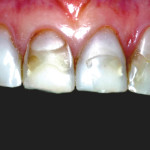

Trattamento combinato parodontale e restaurativo per la riabilitazione del settore anteriore

Il caso clinico descrive un approccio inter-disciplinare di successo per il trattamento dei settori anteriori compromessi dal punto di vista estetico. In una prima...